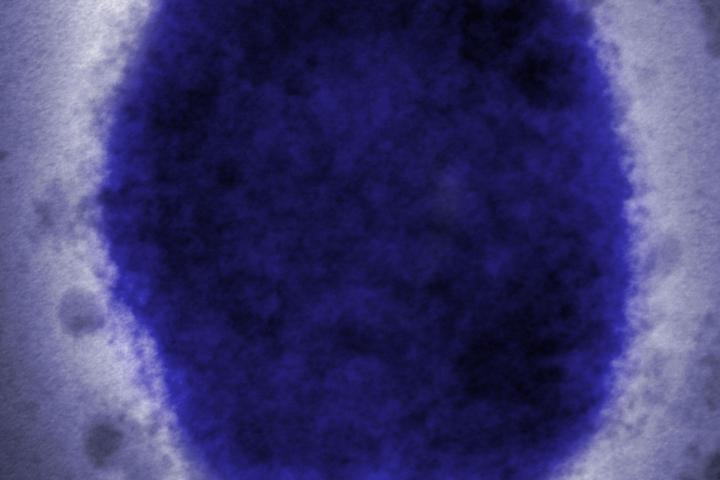

No estamos ante un nuevo agente patógeno desconocido. El virus fue descubierto en 1958, cuando ocurrieron dos brotes de una enfermedad similar a la viruela en colonias de monos mantenidos para labores de investigación. El primer caso humano de viruela del simio fue notificado en agosto de 1970 en la República Democrática del Congo. Desde entonces, el virus ha sido estudiado y se ha realizado un seguimiento de los casos y brotes que ha originado.

El virus de la viruela del simio es un virus de ADN relativamente grande que muta a menor velocidad que virus de ARN como los coronavirus o los influenzavirus. Los virus de ADN tienen mejores sistemas para detectar y reparar mutaciones que los virus de ARN, lo que significa que es poco probable que el virus de la viruela símica haya mutado repentinamente o que lo haga con una tasa elevada como para alcanzar una excelente transmisión humana o manifestar una variabilidad alta.

Esta situación provoca que, una vez superada la enfermedad, el individuo adquiera inmunidad a largo plazo contra el virus. Hasta la fecha se han caracterizado dos clados genéticos del virus de la viruela del mono, el clado de África Occidental y el clado de África Central. Ambos están separados geográficamente y tienen diferencias epidemiológicas y clínicas definidas. La secuencia de ADN muestra que el virus causante del brote actual es del tipo leve que circula por África Occidental y que está estrechamente relacionado con los virus de la viruela del simio detectados en el Reino Unido, Singapur e Israel en 2018 y 2019.